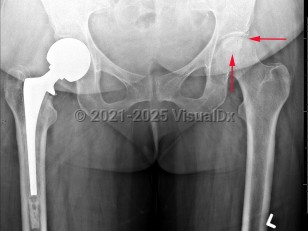

Grade / classification system: The Ficat classification system is based on plain x-rays and the patient's symptoms.

- Stage III: "crescent sign," abnormal contour or flattening of the femoral head from subchondral collapse with joint space preserved